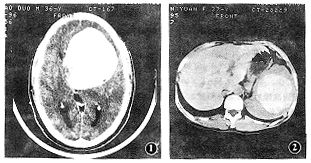

例1 男,36岁。行走不稳1年,头痛1个月余。神经系统查体未见异常。CT表现:左额、颞叶近中线可见一巨大高密度占位病变,CT值约75HU,9 cm×8 cm×8 cm大小,类圆形,边缘光滑,与周围脑组织分界清晰,其边缘可见小低密度灶及钙化灶。左侧脑室、三脑室、鞍上池受压,中线略向右移位。增强扫描病变无强化(图1)。手术所见:肿物位于鞍区,向左颞、额扩展,大小约9 cm×9 cm×7 cm,穿刺放出巧克力样囊液约90 ml,囊内可见实性巧克力样及油脂样物质,囊壁完整。病理诊断:表皮样囊肿。

例2 女,37岁。大便次数增多,稀便3个月,腹部肿物3天。体检发现脾大,于肋下3 cm可触及,质中,表面似不平。既往无腹部外伤史。腹部X线片:未见阳性结石影。CT表现:脾脏增大,占据10个肋单元。脾内可见圆形高密度灶,边缘光滑锐利,与脾实质分界清楚,大小10.4 cm×7.8 cm×7.5 cm,其内密度欠均匀,CT值129~167HU(图2)。冠状重建可见病变几乎占据脾脏,其左右径与脾横径相当。手术所见:脾内见一5 cm×4 cm×4 cm及11 cm×7 cm×6 cm囊腔,其内为黄色胶冻样物,可见数十个散在大小不等质硬结节。病理诊断:脾表皮样囊肿。

图1 颅内表皮样囊肿,起源于鞍区。增强扫描,CT值约75HU,与平扫无明显差别 图2脾表皮样囊肿,脾内可见巨大高密度灶,CT值129~167HU